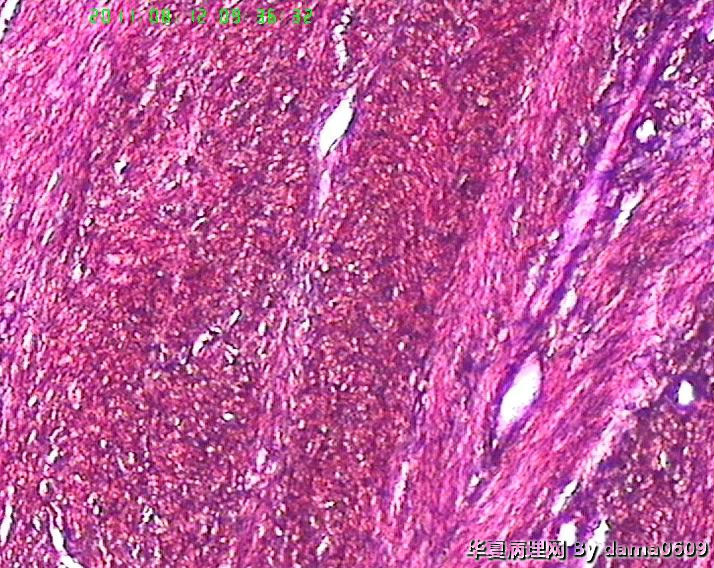

老师好!以前学生也遇到过此情况,偶尔染出的片子的细胞核的上方会出现黑色的异物,多见于子宫平滑肌瘤的片子。很影响观察核的形态、核分裂像。初以为是苏木素杂质,而且不经常出现,所以没在意。最近此现象很严重,许多的片子都出现此情况,反复过滤苏木素不见好转,新配苏木素也是如此。经过仔细观察,现发现似乎不是杂质,是细胞核上方覆盖着小气泡(如图),不知何故,如何解决??另外一个问题,我们的片子封片后经常出现斑片状或整张片子模糊,似乎树胶没有封到(如图),不只是脱蜡不干净,还是脱水出问题?此想象并不是出现在所有的一批片子上,而是个别。请老师们帮助指点。谢谢。

原因:细胞核为黑色,是因为显微镜光源的光线未能顺利穿过细胞核或是期间发生了折射引起了细胞核发黑。

分析:经过仔细观看你发上的图片,几乎可以肯定细胞核内地物质为水。因为如果是气泡折光不会如此严重,会出现类似同心圆的黑泡,而水是几乎光线很难穿过除非大的水泡,所有我认定主要凶手为组织脱水不彻底或切片从无水里取出暴露在空气中时间较长引起了潮化。

解决:更换脱水酒精,切忌封片前不要在空气中暴露时间过长,不然你就是全用无水脱也无济于事。

总结:楼主如果按规定步骤走,按规定更换脱水液,还出现这种情况,就说明技术室湿度过大,封片一定要及时!呵呵 楼上不会是南方人吧,这种情况南方多见!

因为不知道你的脱水、染色程序,所以,只能推测性的回答你的问题了(如有不对的的地方,请指教)。细胞核的上方会出现黑色的异物从第图5、6、7、8、9中可以中看的很清楚,看着不像是苏木素结晶,从平滑肌细胞核上看着有的细胞有些像苏木素深染了(有几个细胞核染的类似图5、6、7、8、9中的,这几个肯定不是深染),是有什么东西覆盖在细胞核上,我觉得应该是苏木素-伊红以后的问题(封片过程中脱水透明不彻底造成的,如果是干封,酒精中的水分带带二甲苯中,透明后,吹干在封片后,有可能出现这种情况,湿封也是一样,封片后,玻片的组织上出现小的水泡,可能出现这种情况。你试试把脱水透明的无水酒精和二甲苯换了看看);封片后经常出现斑片状或整张片子模糊,似乎树胶没有封到,从图10来看很明显是我刚才提到的,是脱水不好(无水酒精不纯,而把水份带到二甲苯中),封片后就出现这种情况了(这个不是气泡),后面的图13、14怎么看着像没封片一样(应该不会是胶的问题吧?)你先换换酒精和二甲苯试试!